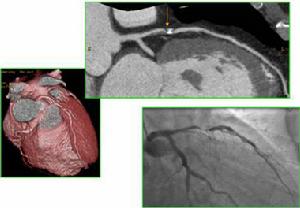

2、冠狀動脈造影檢查:

約2/3的病人顯示至少1支冠狀動脈主支存在嚴重的粥樣硬化性阻塞性病變,變異型心絞痛常發生於阻塞性病變l厘米以內或其附近處。其餘1/3病人在變異型心絞痛發作時可見到缺血區變異型心絞痛,緩解期或未發作時,冠狀動脈正常。

疾病診斷依據發作時無誘因,發作劇烈且持續時間較長的臨床特徵,根據心電圖ST段抬高和T波高尖,可診斷為變異型心絞痛。發作期間冠狀動脈造影有助於診斷。

冠狀動脈造影正常者,可考慮採用誘發試驗幫助診斷。臨床上常用為麥角新鹼、乙醯膽鹼和過度通氣等,其中以麥角新鹼最為敏感,可從小劑量如0.05mg靜脈開始,逐漸增加劑量直至出現陽性反應如心絞痛發作、心電圖ST段抬高和冠狀動脈造影示變異型心絞痛為止或劑量達0.4mg時中止。冠狀動脈誘發試驗具不一定危險性,故應當慎重,在心肺復甦設備、搶救藥物等設施一應俱全的心導室中時進行,以便一旦出現陽性反應,立即冠狀動脈內注射硝酸甘油,及時解除變異型心絞痛。